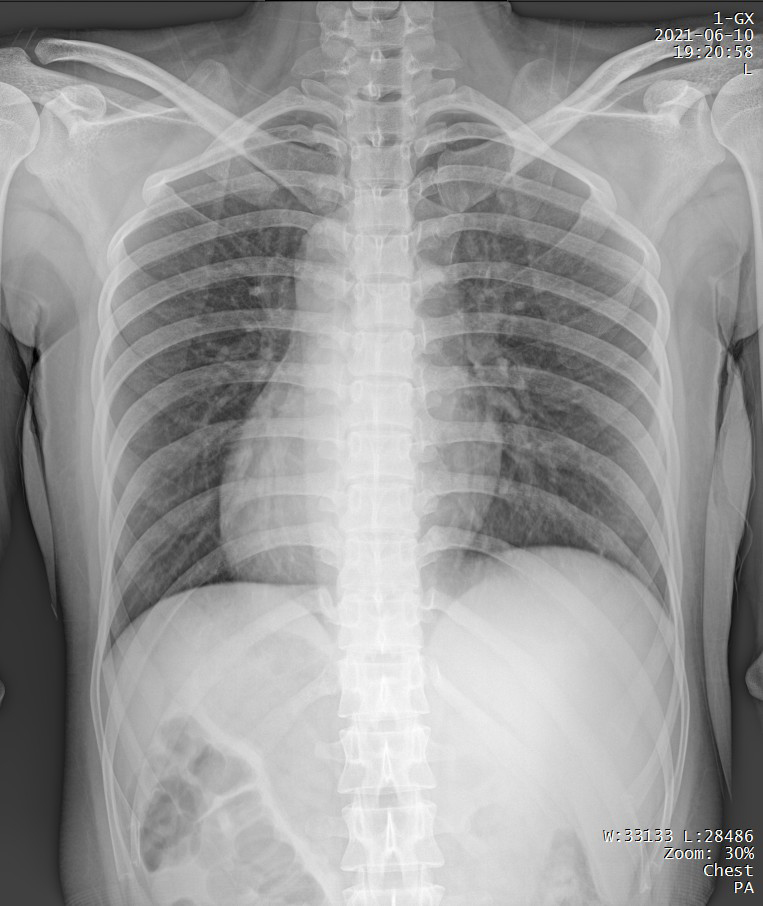

Clinical picture

临床图片